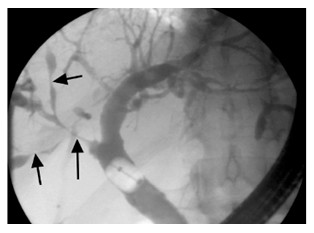

ERCP显示:多发性肝内胆管狭窄